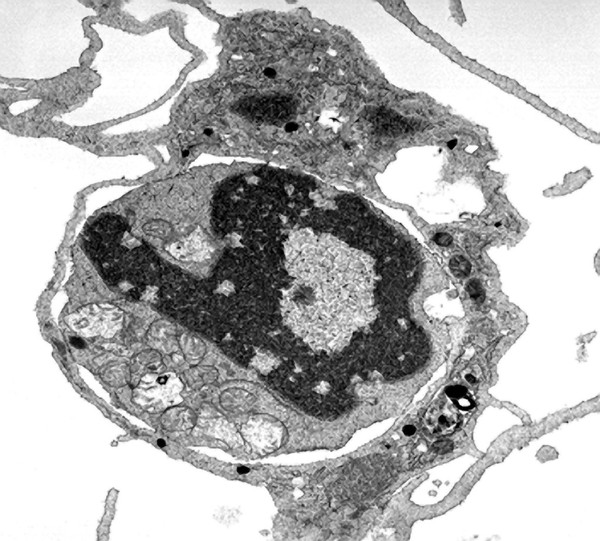

TEM cell being ingested by phagocytosis

Dr Jeremy Skepper- Books